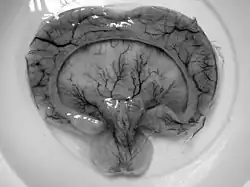

| Gross pathology specimen from a case of alobar holoprosencephaly, a clinical manifestation of Young–Madders syndrome first described as a new condition by doctors Young and Madders in 1987. |

Young–Madders syndrome, alternatively known as pseudotrisomy 13 syndrome or holoprosencephaly–polydactyly syndrome, is a genetic disorder resulting from defective and duplicated chromosomes which result in holoprosencephaly, polydactyly, facial malformations and intellectual disability, with a significant variance in the severity of symptoms being seen across known cases.[1] Many cases often suffer with several other genetic disorders, and some have presented with hypoplasia, cleft lip, cardiac lesions and other heart defects. In one case in 1991 and another in 2000 the condition was found in siblings who were the product of incest. Many cases are diagnosed prenatally and often in siblings.[1] Cases are almost fatal in the prenatal stage with babies being stillborn.